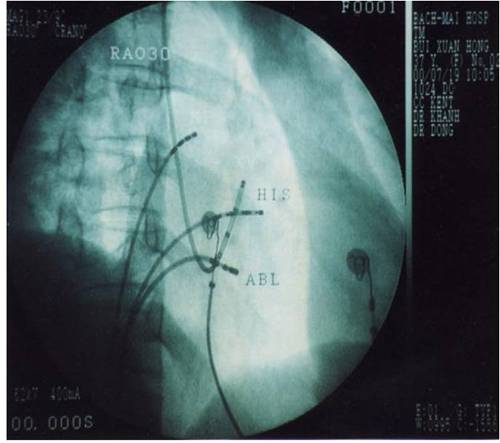

Điều trị cơn tim nhanh vào lại nút nhĩ thất dựa trên cơ sở việc triệt đốt một trong hai đường dẫn truyền qua nút nhĩ thất, đường nhanh hoặc đường chậm. Ngày nay, hầu hết các trung tâm tim mạch trên thế giới đều đồng thuận việc triệt bỏ đường chậm vì có tỉ lệ thành công cao hơn và ít biến chứng gây blốc nhĩ thất hơn. Ống thông đốt sẽ được đưa qua tĩnh mạch đùi tới vị trí triệt đốt đường dẫn truyền chậm ở vùng mô nhĩ phải nằm giữa bờ van hai lá và lỗ xoang tĩnh mạch vành, cách nút nhĩ thất khoảng 1-2 cm (còn gọi là vùng đáy tam giác Koch). Xác định vị trí đường chậm dựa vào điện đồ ghi được tại đầu điện cực đốt và hình ảnh giải phẫu trên X quang.

Hình 11: Vị trí các ống thông trên hình ảnh X quang trong triệt đốt đường chậm ở tư thế nghiêng trái 30 độ (trái) và nghiêng phải 30 độ (phải): NP: điện cực cùng cao nhĩ phải, His: điện cực vị trí bó His, XV: điện cực xoang vành, TP: điện cực mỏm thất phải, Abl: điện cực triệt đốt được đưa vào vùng đáy của tam giác Koch, dưới vị trí điện cực bó His khoảng 2 cm và ngang mức với lỗ xoang vành.